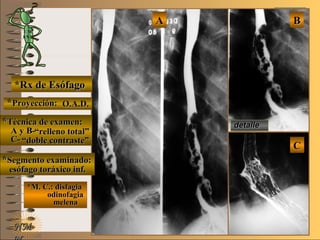

*Rx de Esófago*Rx de Esófago

**Proyecciones:Proyecciones:

A-A-

B-B-

C-C-

**Técnica de examen:Técnica de examen:

**Segmento examinado:Segmento examinado:

*M. C.:paciente adulto con*M. C.:paciente adulto con

disfagia y pérdidadisfagia y pérdida

de pesode peso

detalledetalle

AA BB CC

O.A.D.O.A.D.

FrenteFrente

O.A.I.O.A.I.

““doble contraste”doble contraste”

esófago toráxicoesófago toráxico

A-A-El examen es normal o patológico?El examen es normal o patológico?

Examen patológico de esófago toráxico con téc-Examen patológico de esófago toráxico con téc-

nica de doble contraste en proyecciones O.A.D.nica de doble contraste en proyecciones O.A.D.

frente y O.A.I.frente y O.A.I.

B-B-La patología es congénita o adquirida?La patología es congénita o adquirida?

Patología adquiridaPatología adquirida

D-D-La misma es neoplásica o no neoplásica?La misma es neoplásica o no neoplásica?

Patología adquirida orgánica neoplásicaPatología adquirida orgánica neoplásica

E-E-Puede describir la o las imágenes patológicas?Puede describir la o las imágenes patológicas?

Se identifica en el borde posterior de tercio medioSe identifica en el borde posterior de tercio medio

de esófago toráxico una imagen elevada, sesil,de esófago toráxico una imagen elevada, sesil,

de bordes irregulares que ocupa 2/3 de la luzde bordes irregulares que ocupa 2/3 de la luz

esofágica, compatible con C.A. avanzado tipoesofágica, compatible con C.A. avanzado tipo

I deI de BorrmannBorrmann UNTUNT

C-C-Dicha patología es orgánica, funcional o mixta?Dicha patología es orgánica, funcional o mixta?

Patología adquirida orgánicaPatología adquirida orgánica